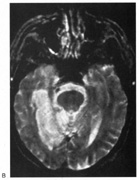

DISORDERS OF COLOR PROCESSING Cerebral Dyschromatopsia Cerebral (central) achromatopsia refers to complete loss of color perception, whereas cerebral dyschromatopsia indicates some residual color perception, as is most often the case. Both are rare. Hemiachromatopsia refers to color loss restricted to the contralateral hemifield,234,235 and may be more common but under-recognized. Achromatopsic patients generally are symptomatic, complaining that the world appears in shades of gray.236–239 Some also report that the world appears less bright240 or has a “dirty gray” tinge.241 Less frequently, patients report a tinge to the world, as if peering through a colored filter.242 Daily activities that use color discrimination are impaired, such as distinguishing coins, stamps, or traffic lights: A good account exists of the experience of an achromatopsic artist.243 Effects on “color constancy” are an important issue. The wavelengths reaching the eye from an object depend on both its reflectant properties and the light illuminating the scene. Yet, the color of objects remains stable under a wide range of environmental and lighting conditions.244,245 For instance, an apple continues to look red in sunlight, incandescent light, and fluorescent light, in an orchard or a grocery display. This ability to “discount the illuminant” depends on neural computations in retina and cortex.244 These computations likely average the spectral luminance over large regions of the surrounding background to deduce the nature of the illuminant, and this information is then taken into account to derive the true color of any object in the scene.244,246 A defect in color constancy should result in color percepts that vary with changes in illumination. Patients with achromatopsia have a more severe deficit, in that they lack any color percept at all. Testing such patients for constancy of something they do not perceive is paradoxical, but this can be done on dyschromatopsic patients, who have some residual hue sensitivity. Some studies have shown that color constancy is impaired in these patients.247–250 These patients all had bilateral lingual and fusiform gyral lesions, except for one unilateral case.248 Not all color perception is lost in achromatopsia. Some color input from the cones and retinal ganglion cells of the parvocellular pathway still can be processed. Thus, both trichromacy and color opponency have been shown in photopic spectral sensitivity curves247,251,252 and evoked potential or psychophysical measures of chromatic contrast sensitivity.252,253 Likewise, performance with anomaloscope testing can resemble an anomalous trichromat rather than a monochromat, despite the experience of the world as monochromatic “shades of gray.”254 Achromatopsics can use color-opponent signals to locate chromatic boundaries, even though they cannot perceive the colors that determine those boundaries. Thus achromatopsics can detect the movement of chromatic stimuli,255,256 even performing at normal levels with suprathreshold chromatic contrast.257 This indicates that wavelength variation is still perceived, even if color is not. Achromatopsia is seldom an isolated finding. Most commonly it forms one component of a tetrad that includes superior quadrantanopia, prosopagnosia, and topographagnosia. Superior field loss is almost always present, because the ventral occipito-temporal lesion that causes achromatopsia frequently extends into the inferior calcarine cortex or optic radiation. Similarly, only a few cases without prosopagnosia have been reported.258 Experimental testing has revealed in some patients a problem with detecting stimuli with low salience,259 which has also been described in monkeys with V4 lesions, and thought to indicate inefficient attentional allocation in form processing. Other occasionally associated defects include visual object agnosia,251,260 alexia in achromatopsic patients with right hemianopia,238,258 and amnesia with additional ventral temporal lobe damage.238,260 Achromatopsia is caused by lesions of the lingual and fusiform gyri,245,261 as confirmed by modern imaging.240,241,251,254,258,262 Lesions of the middle third of the lingual gyrus or white matter behind the posterior tip of the lateral ventricle may be critical.240,263 Bilateral lesions are necessary for complete achromatopsia. In monkeys, color-selective responses are found in area V4.245 However, lesions of V4 do not impair hue perception significantly.264–269 Rather, defects in chromatic perception require extensive bilateral lesions, including areas TE and TEO.270,271 In humans, functional imaging reveals several areas involved in color processing, notably a V4 homologue and a second area named V4 alpha or V8 in the fusiform gyrus,272,273 as well as other more distant regions.274–276 Thus color processing involves a network of regions, and it is probable that a severe achromatopsic defect may require damage to or disconnection of several components of the network, rather than just a lesion of a single region like the human V4 homologue.267,277,278 Achromatopsia is most often caused by strokes. Bilateral sequential or simultaneous infarctions in the territories of both posterior cerebral arteries can occur, or multiple infarcts may result from a coagulopathy.279 Achromatopsia may be the first symptom of a stroke or the outcome of an initial cortical blindness. Other bilateral lesions causing achromatopsia include herpes simplex encephalitis,251 cerebral metastases,258 repeated focal seizures,280 focal dementia,281 and even migraine aura, causing a transient achromatopsia.282 Temporo-occipital white matter damage has caused a reversible dyschromatopsia in one patient with carbon monoxide poisoning,283 a condition that usually causes an apperceptive agnosia with spared color perception.245 HEMIACHROMATOPSIA. Achromatopsia in the contralateral hemifield alone can follow unilateral right or left occipital lesions (Fig. 18). Patients are typically asymptomatic until the defect is demonstrated on examination.234,235 Hemiachromatopsia is usually associated with a superior quadrantanopia;234,235,241 therefore, the color defect is only demonstrable in the remaining inferior quadrant. The preserved color vision in the ipsilateral hemifield allows normal or near-normal performance on centrally viewed tests of color vision such as pseudoisochromatic plates. The incidence of hemiachromatopsia is probably underestimated, given its asymptomatic nature and the failure of routine clinical color tests to detect its presence.